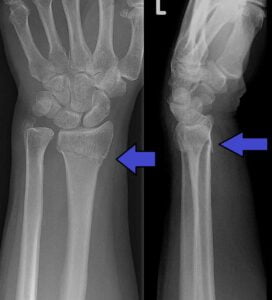

- X Rays: AP, lateral and oblique

- Comment on…

- Type of distal radial fracture?

- Any displacement?

- Any joint involvement?

- Associated Ulnar Styloid fracture?

Distal Radial Fracture Radiographic Criteria (4,5)

| Measurement | Radiograph required | Normal | Acceptable Limits | Post-Reduction Acceptable Limits |

|---|---|---|---|---|

| Radial Inclination | AP | ~23o | Change < 5o | |

| Radial Height | AP | ~13mm | <5mm shortening | <3mm shortening |

| Intra-articular Step | AP | Congruous | <2mm step | <2mm step |

| Angulation | Lateral | ~11o | Dorsal angulation <5o or <20o of contralateral side | Dorsal angulation <10o |